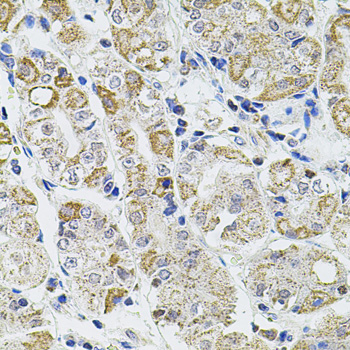

Immunohistochemistry of paraffin-embedded human prostate using Caspase-12 at dilution of 1:100 (20x lens).

Immunohistochemistry of paraffin-embedded human stomach using Caspase-12 at dilution of 1:100 (40x lens).